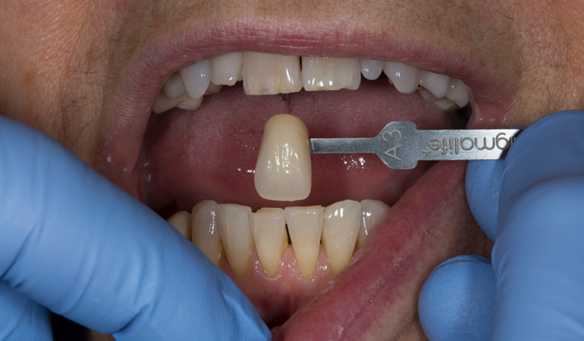

- “Don’t like teeth colour”

- Yellowing teeth